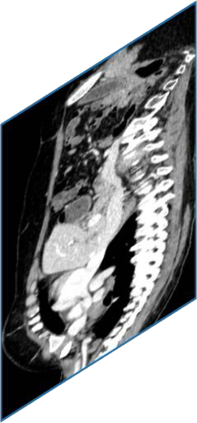

Due to the constraints of the imaging device and high cost in operation time, computer tomography (CT) scans are usually acquired with low intra-slice resolution. Improving the intra-slice resolution is beneficial to the disease diagnosis for both human experts and computer-aided systems. To this end, this paper builds a novel medical slice synthesis to increase the between-slice resolution. Considering that the ground-truth intermediate medical slices are always absent in clinical practice, we introduce the incremental cross-view mutual distillation strategy to accomplish this task in the self-supervised learning manner. Specifically, we model this problem from three different views: slice-wise interpolation from axial view and pixel-wise interpolation from coronal and sagittal views. Under this circumstance, the models learned from different views can distill valuable knowledge to guide the learning processes of each other. We can repeat this process to make the models synthesize intermediate slice data with increasing inter-slice resolution. To demonstrate the effectiveness of the proposed approach, we conduct comprehensive experiments on a large-scale CT dataset. Quantitative and qualitative comparison results show that our method outperforms state-of-the-art algorithms by clear margins.